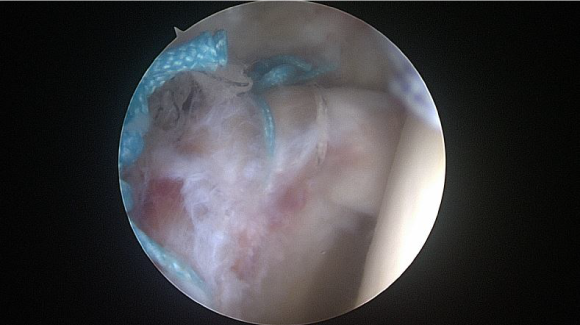

ㆍ비구순 연골파열 및 파열된 비구순을 봉합하는고관절 관절내시경 영상 (2021.10.15)

ㆍ환자 동의를 받은 자료이며, 이미지 사진은 실물과 다를 수 있습니다.